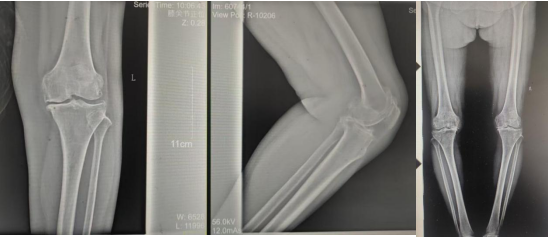

術(shù)前影像資料

張女士于10年前勞累后左膝疼痛,干活后疼痛較重,陰雨天及受涼時(shí)疼痛明顯,行走時(shí)可聞及關(guān)節內異響,時(shí)有“打軟腿”現象,曾到附近多家醫院診治,給予膝關(guān)節針灸、膏藥外貼、口服藥物等“保守”治療,治療后疼痛癥狀略有好轉,但易復發(fā);近2年患者左膝關(guān)節疼痛逐漸加重,行走跛行,下蹲及上下樓梯困難,活動(dòng)時(shí)疼痛明顯,休息、保守治療后疼痛無(wú)明顯好轉。

張女士的鄰居看她上下樓如此困難,日常生活都很受影響,因其以前在我院看過(guò)腰椎,效果良好,故介紹張女士來(lái)我院找萬(wàn)昌勝主治醫師進(jìn)行咨詢(xún)問(wèn)診。萬(wàn)醫生了解情況后帶她到我院關(guān)節外科進(jìn)行更專(zhuān)業(yè)的診治。關(guān)節外科門(mén)診醫師結合癥狀體征及影像學(xué)檢查,建議入院手術(shù)治療,以“左膝骨性關(guān)節炎伴膝內翻、高血壓病”收住入院。